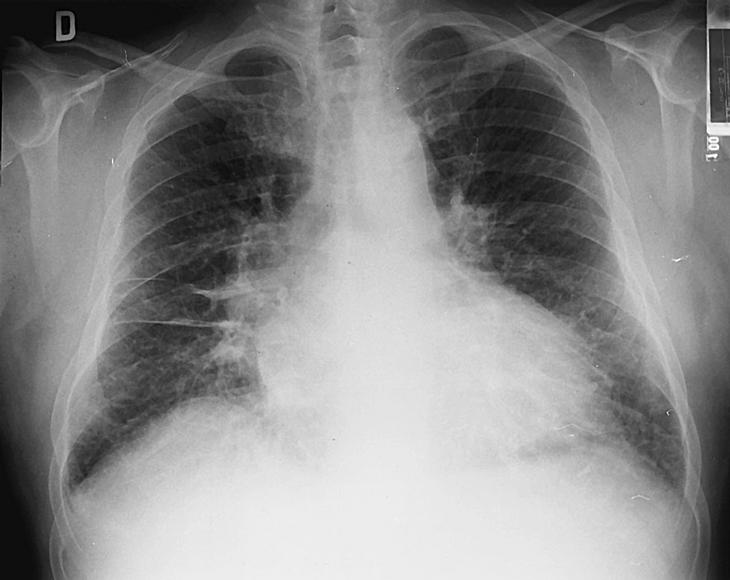

Esta enfermedad es el paradigma de la insuficiencia cardíaca con función sistólica deprimida, con todos los signos y síntomas propios de esa situación. ☤

Las embolias se producen con más frecuencia que en otras causas de insuficiencia cardíaca, probablemente en relación con la gran dilatación de las cámaras cardíacas.

Puede presentarse debilidad y desplazamiento hacia abajo y hacia afuera del impulso apical, así como tercer y/o cuarto ruidos, pulso alternante, datos de hipertensión pulmonar y fallo derecho en casos avanzados.